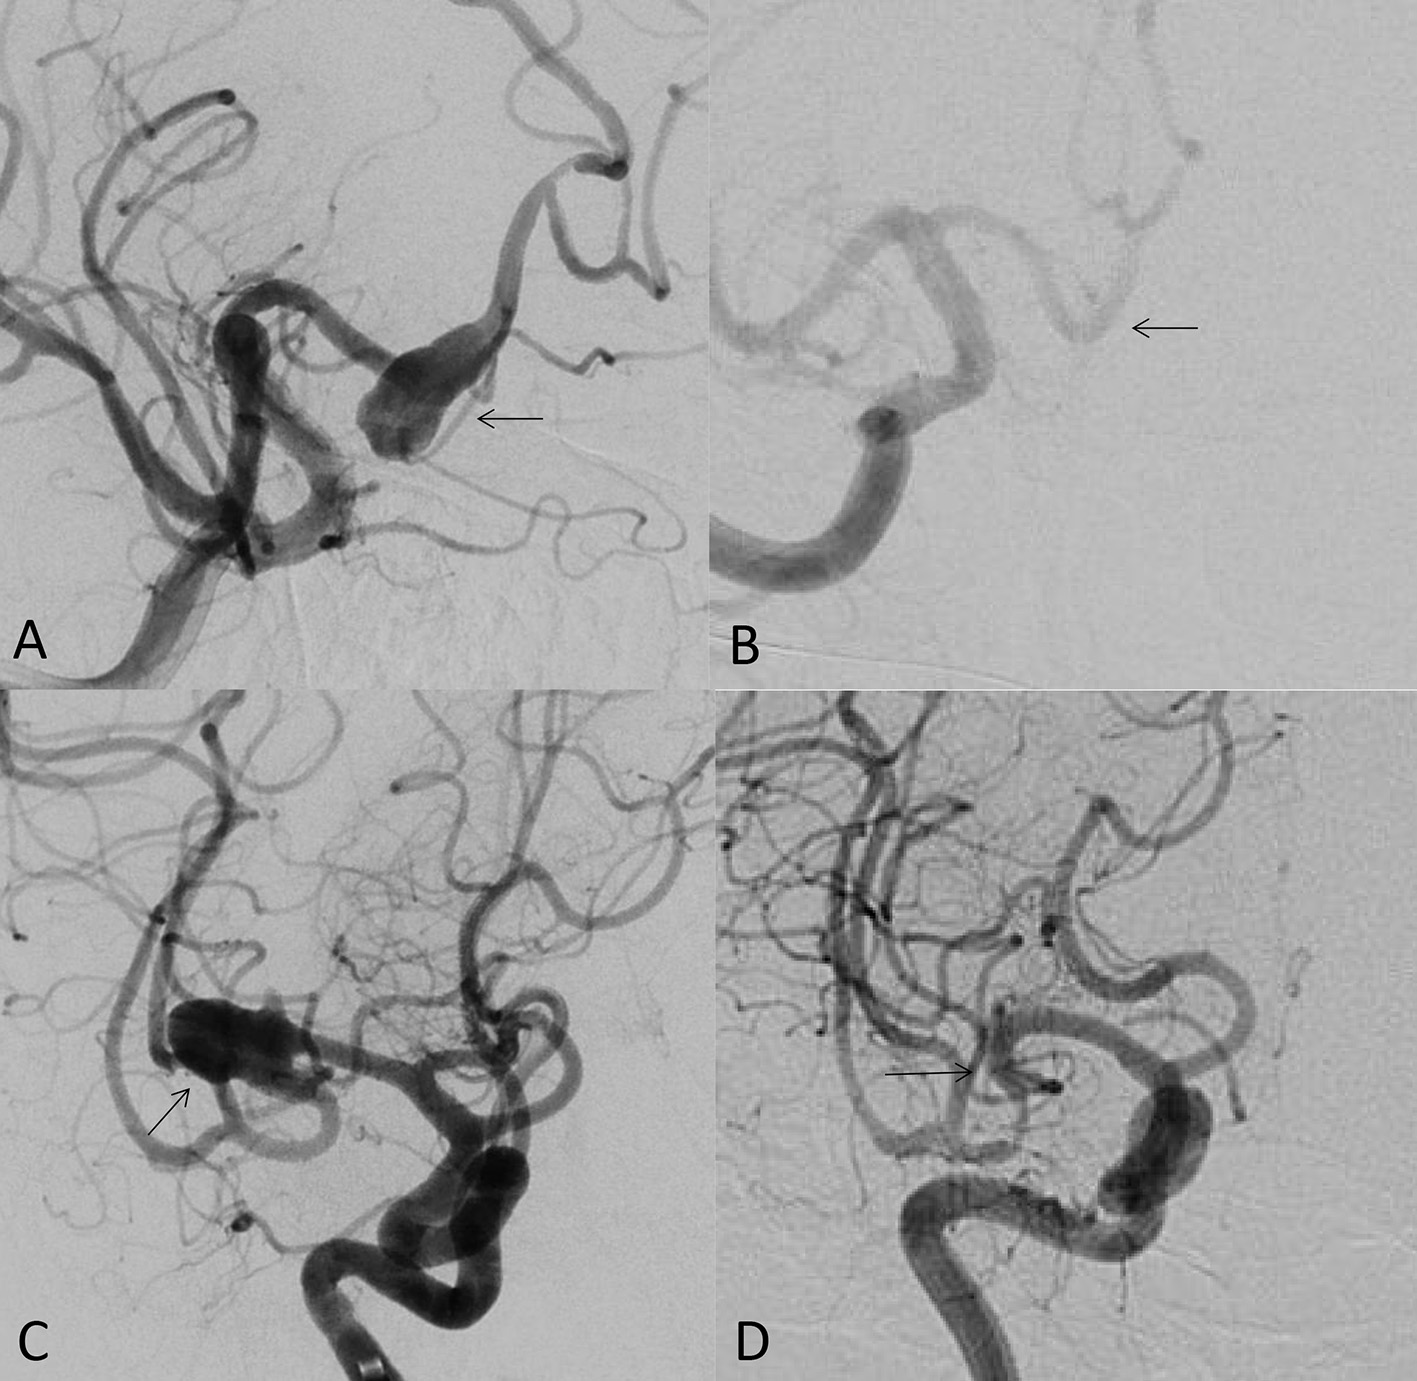

As the first FDA certified FD, the pipeline embolization device (PED; Medtronic Neurovascular, Irvine, California, USA) is still the most popular FD at present. Its safety and effectiveness of the off-label use have been widely published. Its clinical use has expanded from unruptured internal carotid artery aneurysms to the most cerebral aneurysms, such as anterior cerebral artery, middle cerebral artery and posterior circulation aneurysms (including posterior cerebral artery and posterior inferior cerebellar artery aneurysms; Figures 1A–D). It is a good option for ruptured and unruptured aneurysms with incorporated perforating arteries. FD has become the first-line treatment for blister-like aneurysms (5). There are also reports on the FD treatment of carotid cavernous fistulas. In our center, the FD has replaced the coil embolization in most of unruptured aneurysms due to its low complication rate, low recurrence rate and high occlusion rate (3). In a meta-analysis including 11 studies (6), the occlusion rates of unruptured aneurysms at 1 year, 1–2 years, 2 years, 3 years, and 5 years follow-up were 77%, 87.4%, 84.5%, 89.4%, and 96%, respectively. There were 5% long-term in-stent stenosis, one delayed ischemic stroke and no delayed hemorrhage of aneurysm.

Figure 1

(A) 49-year-old male, unruptured aneurysm of the right anterior cerebral artery (arrow); (B) the 7 months control angiogram after PED treatment showed that the aneurysm was completely occluded (arrow); (C) 53-year-old female, the right middle cerebral artery bifurcation aneurysm (arrow); (D) the control angiogram after 9 months showed that the aneurysm was completely occluded (arrow).